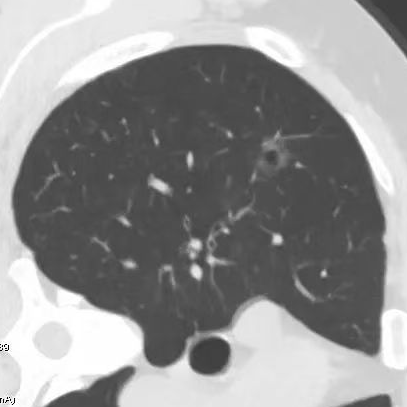

健康直通车: 健康是生命的宝贵财富,也是幸福生活的基石。为了更好地服务广大百姓,传播健康知识,葫芦岛市第二人民医院推出“健康直通车”专题栏目,将专业的医学知识以通俗易懂的方式传递给每一位市民,掌握科学的疾病预防方法,共同构筑健康中国的坚实基石。 什么是肺结节 肺结节是指肺内直径小于或等于3cm的类圆形或不规则形病灶,影像学表现为密度增高的阴影。大于3cm的称肿块。肺结节依其密度不同可分为实性结节、部分实性结节、磨玻璃结节,其中部分实性结节的恶性可能性最大,磨玻璃结节次之,实性结节尤其是小的实性结节结节最可能是良性的。 肺结节的常见病因 1、良性(约90%) 🔸 感染:结核、真菌、细菌性肺炎后遗留的瘢痕; 🔸 非感染:错构瘤(良性肿瘤)、炎性假瘤、血管瘤等。 2、恶性(约10%) 🔸原发性肺癌(如腺癌、鳞癌); 🔸转移性肿瘤(其他器官癌症转移至肺)。 如何根据影像判断肺结节性质 1、依据结节大小判断 🔸小于0.5cm的肺结节绝大多数都是良性的,属于微小结节。即使部分小于0.5cm肺结节是恶性的,但是适当的观察不影响预后。每年复查一次胸部CT就可以。 🔸大于0.5cm持续存在的纯磨玻璃结节,观察6个月,若持续存在,不管有无进展均多数是恶性的,视患者意愿,手术可以立即做也可观察至进展再做,不影响预后。 🔸大于0.8cm的部分实性结节恶性可能性非常大,应积极评估结节边缘毛刺、分叶、胸膜凹陷等征象。 🔸若实性部分大于0.5cm,恶性率显著提高。若在3~6个月随访期间实性部分增大或者总体部分增大,都可以考虑手术切除。而即使小于0.8cm的部分实性结节也需3个月就复查对比。 2、依据肺结节形态 如CT上提示病灶形态不规则、毛刺、分叶、胸膜凹陷、空泡征、血管集束征等,符合恶性肿瘤的征象。 🔸结节与正常肺组织之间界限非常清楚的恶性可能性大。 🔸结节密度不均呈混杂密度或均匀较大纯磨玻璃结节也基本是恶性的。 🔸有胸膜牵拉(不管是肺表面的脏层胸膜还是叶间裂部位的胸膜)的恶性可能性大。 🔸结节有浅分叶、细毛刺,密度较高而与周围肺组织边界不清的恶性可能性大。 🔸磨玻璃或混合磨玻璃结节存在小空洞的恶性可能性大。 🔸影像上似慢性炎表现,而没有炎症相关的其他异常,特别当所谓炎症区域内部或一侧与正常肺组织之间界限非常清楚的基本上是恶性的。 3、从结节发展情况来看 所有随访中增大进展的都需要考虑恶性可能,不进展而持续存在的纯磨玻璃结节也需考虑恶性。 葫芦岛市第二人民医院肺结节诊治中心孙振教授深耕肺结节领域四十余载,凭借对临床实践的执着钻研与深厚积淀,在肺结节精准诊断及鉴别诊断领域形成独到见解。他系统总结海量临床病例,创新性提炼出一套科学化、规范化的肺结节全周期诊疗体系,尤其在早期微小结节的影像特征识别、良恶性风险分层等方面积累了丰富经验,为众多患者提供了精准、高效的诊疗方案。 人民医院·人民名医 孙振 主任医师 三级教授 ·葫芦岛市第二人民医院胸外科主任、肺结节诊治中心主任 ·中国医科大学客座教授 ·原央企总医院著名胸外科专家 ·辽宁省医学会胸外科委员 ·辽宁省抗癌协会肺癌专业委员会委员 ·辽宁省细胞生物学学会食管癌专业委员会理事 ·主持多项科研成果获科技成果奖、科技进步奖、国家专科奖项 医学成就 从事胸外科临床工作近40年,担任胸外科首席专家及科室主任20余年,是我省胸外科领军人物,推动肺癌、食管癌等胸部肿瘤外科的规范化诊疗,在央企总医院牵头成立了肺结节诊疗中心,率先开展CT引导下肺内小结节定位切除,既确切完整切除肺内小结节,又降低肺功能损害。 专业特色 擅长肺癌、食管癌的外科手术和综合治疗,在各类高难度胸外伤手术治疗、胸腔镜微创手术、胸腺瘤手术及复杂并发症处理方面具有高深造诣,尤其擅长肺癌早期诊断,胸部小结节CT早期肺癌的鉴别等。完成各类高难度胸外科手术5000余例,其中微创手术占比达90%,治愈率达98%,多项业务填补省内空白。 开展的高难手术 胸腔镜肺部结节微创手术、肺癌根治术、食管癌根治术、各种纵隔肿瘤切除术、胸骨后甲状腺手术及胸部复合性外伤的抢救手术等。